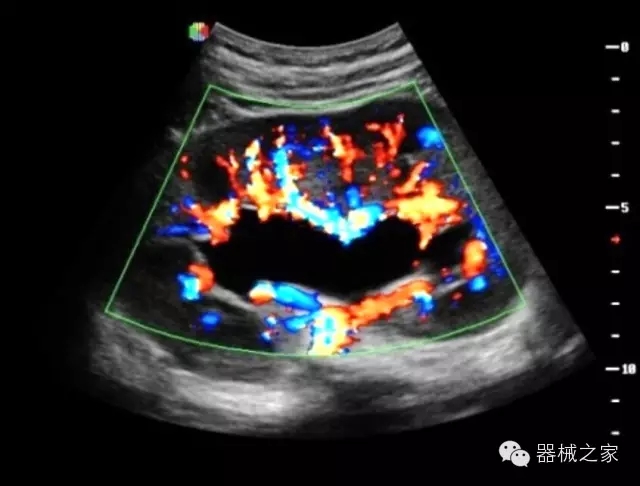

臨床圖片賞析

·獨(dú)有的HoloTM PW 實(shí)時(shí)3取樣門PW成像技術(shù),精確進(jìn)行血管診斷;

·一鍵優(yōu)化B、Color、PW,Auto Doppler自動(dòng)識(shí)別血管位置、偏轉(zhuǎn)角度等,提高工作效率;